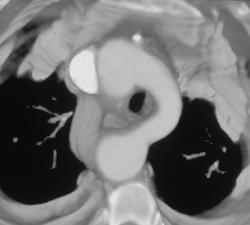

Dilated Aortic Arch